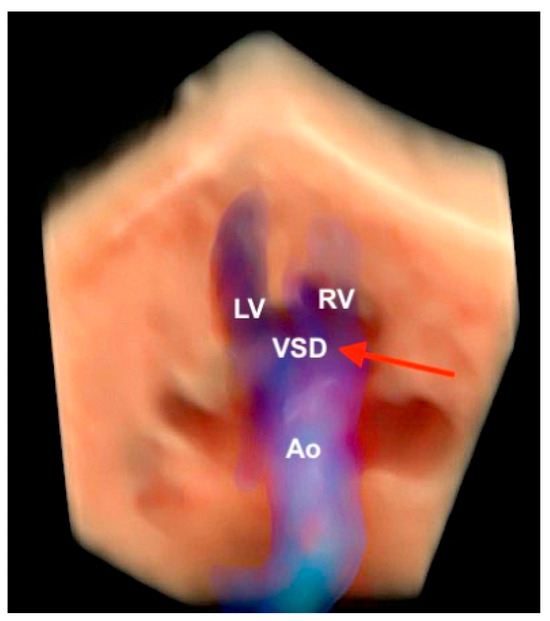

Figure 17.

Realistic Vue with Natural Vue and Transparency mode in a case of complete atrioventricular septal defect. Note the high quality of the image. Virtual light source position; 10 o’clock. LV: left ventricle; LA: left atrium; LV: left heart; RV: right ventricle; VSD: ventricular septal defect; ASD: atrial septal defect; AVV: atrioventricular valve.